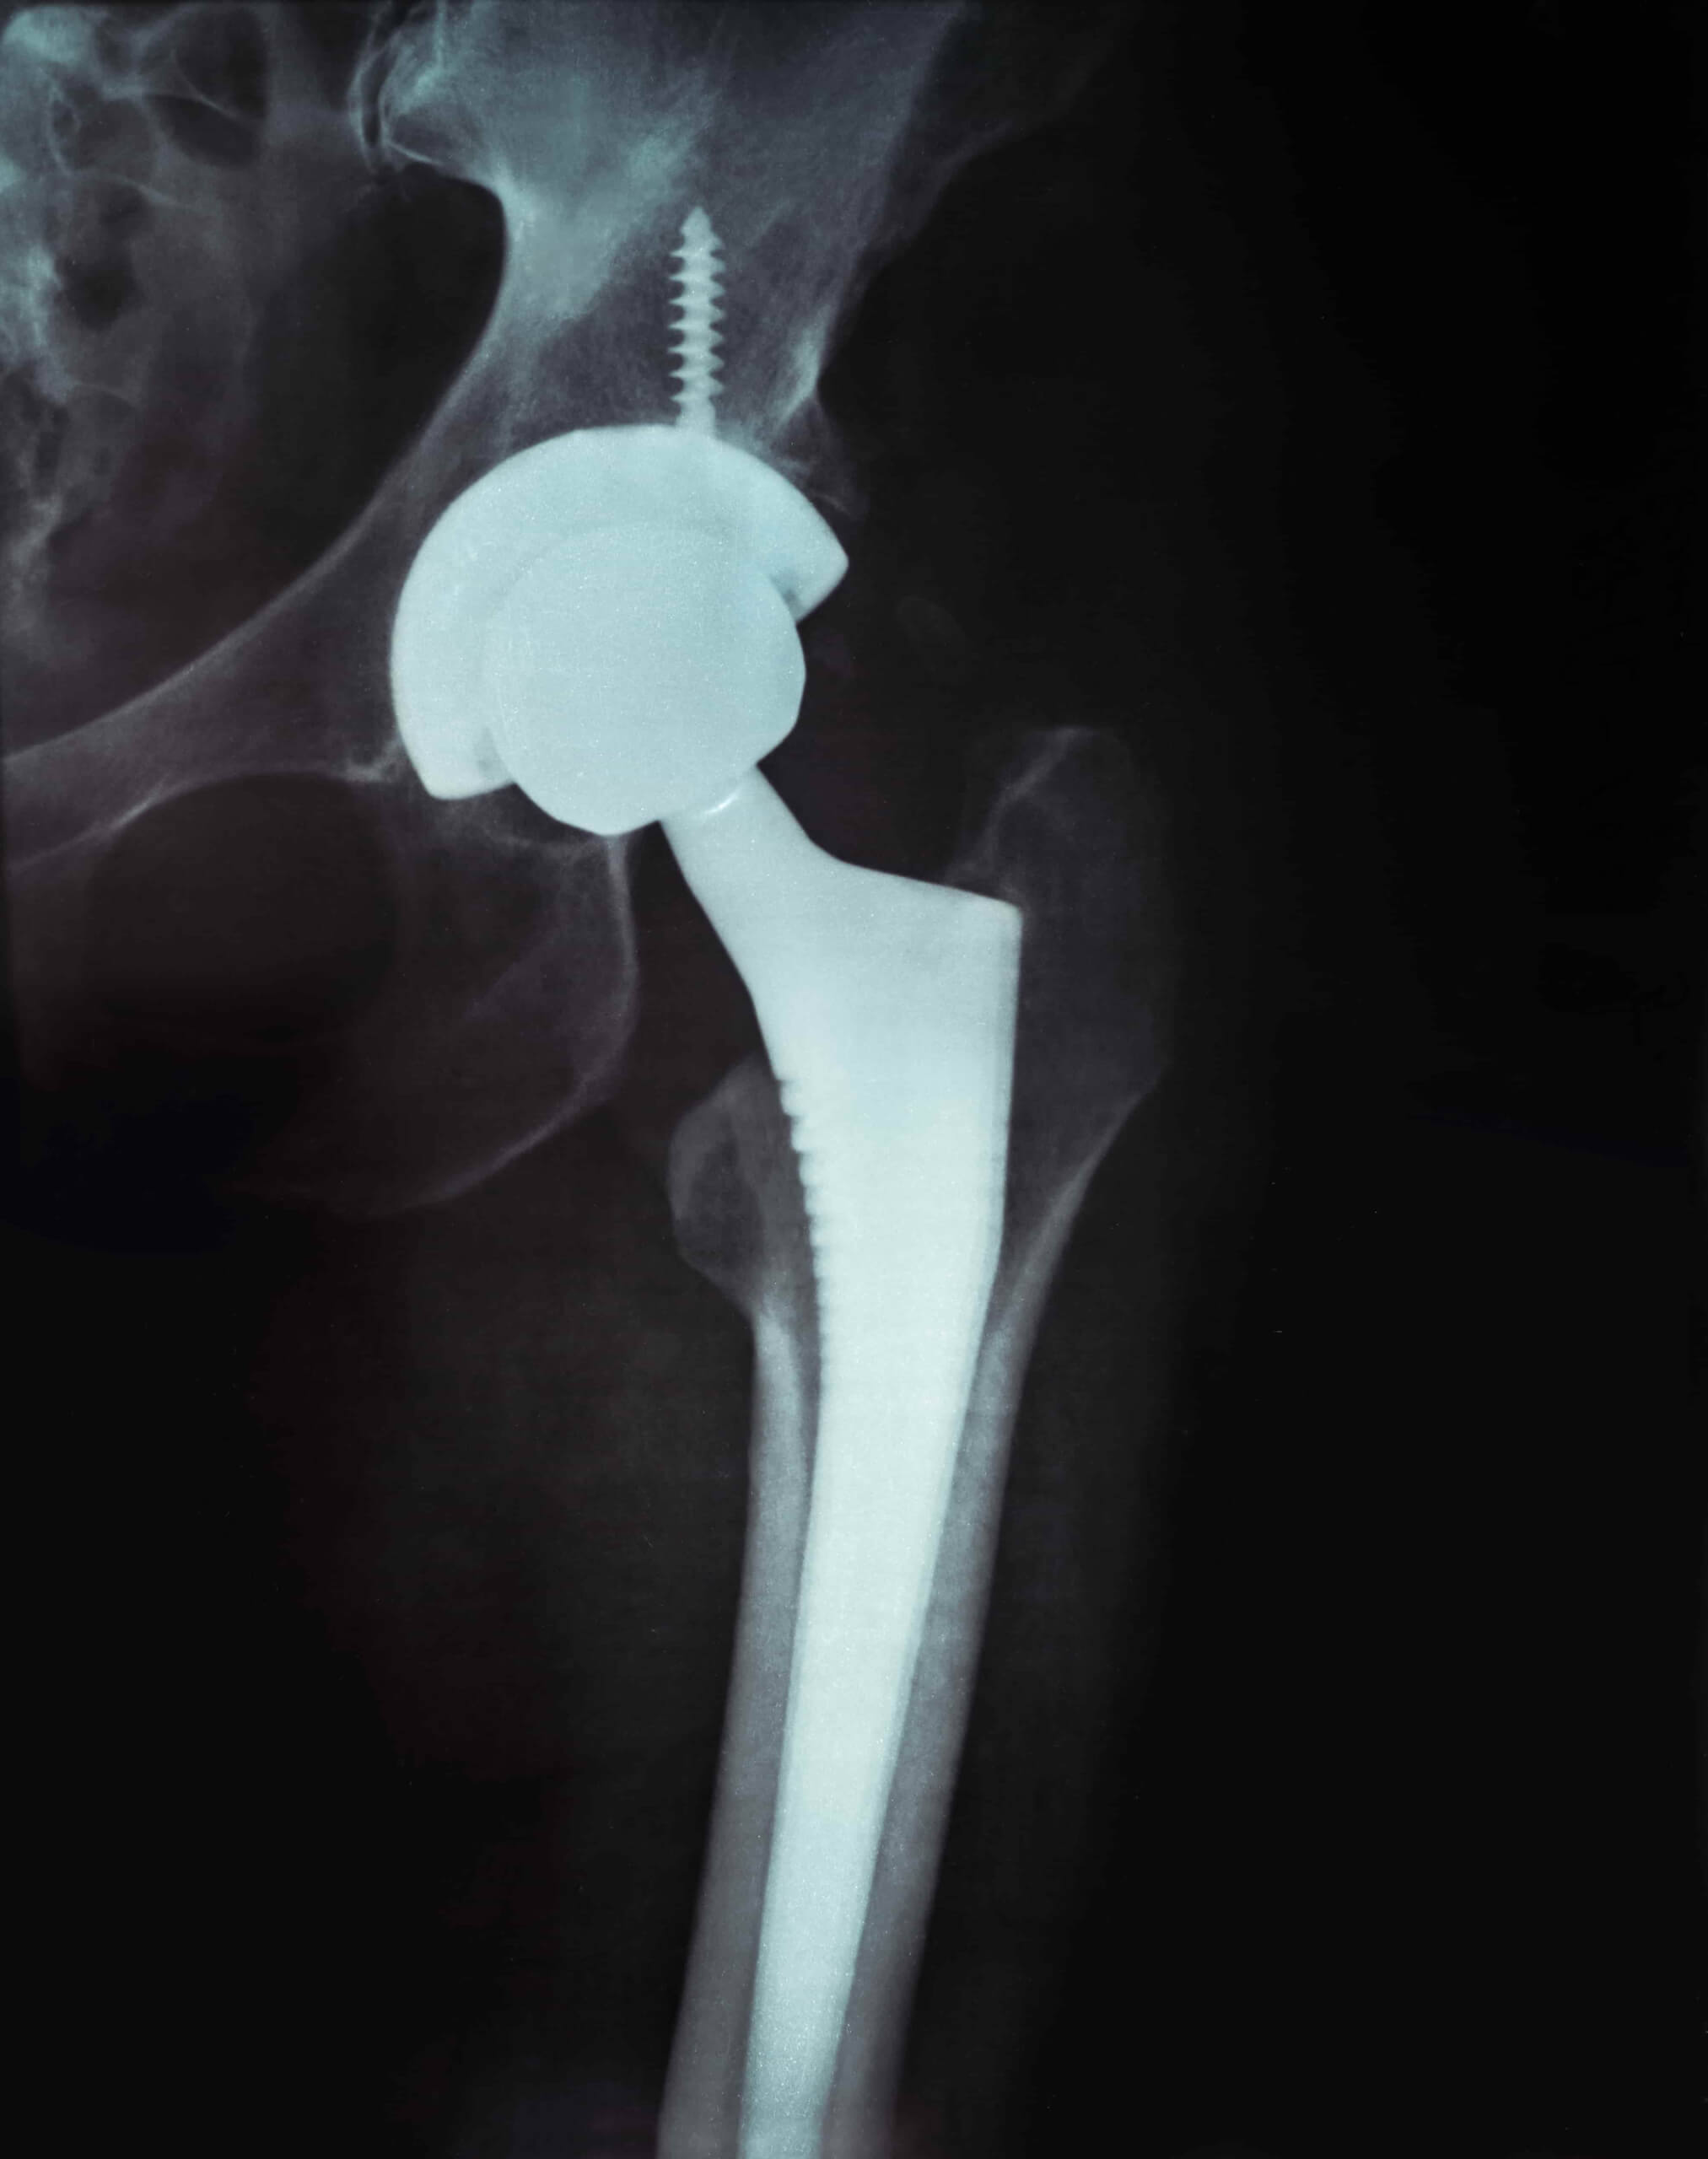

Vstavitev totalne endoproteze kolčnega sklepa je ena izmed najpogostejših operacij sodobne ortopedije z visoko stopnjo uspešnosti posega. Kolčni sklep je obdan s sklepno ovojnico, ki proizvaja sklepno tekočino in s svojim mazilnim učinkom zmanjšuje trenje ter preprečuje obrabo sklepnih površin. Anatomske spremembe v kateremkoli delu kolka, ki jih povzroči poškodba, vnetje ali obraba površin, vplivajo na mehaniko celotnega kolka, ki je s tem funkcionalno prizadet.

Endoproteza kolka je umeten kolčni sklep iz kovinskih materialov, ki ga kirurg z operativnim posegom vstavi na mesto pravega kolčnega sklepa v primeru napredne obrabe hrustanca in/ali artritisa kolčnega sklepa. Okvaro kolčnega sklepa, ki se jo zdravi z endoprotezo kolka največkrat povzroči obraba sklepnega hrustanca, ki je najpogostejši vzrok za pojav bolečin v kolku po 50. letu starosti. Zgodnjo obrabo hrustanca lahko povzročijo tudi različna vnetja (revmatični artritis, putika, luskavica), nekatere razvojne motnje (prirojeni izpah kolka, Perthesova bolezen, zdrs glavice stegnenice) ali pa travmatske poškodbe, ki jih kolčni sklep utrpi v dolgih letih neprekinjenega delovanja.

Simptomatika je v zgodnjih fazah obrabe hrustanca kolka blaga, zajema le bolečino v sklepu, ki se sprva pojavlja ob začetku hoje ali po daljši hoji, spremlja jo lahko motnja cikla hoje (šepanje). V napredni fazi obolenja sklepnega hrustanca je bolečina prisotna tudi v mirovanju, spremlja jo pogosto omejena gibljivost kolčnega sklepa. Slabša mehanika kolčnega sklepa, ki jo povzroči obraba hrustančnih površin vodi v zmanjšano sposobnost hoje in oteženo obvladovanje nujnih življenjskih opravil, predvsem pa povzroča bolečine, ki so občasno visoke intenzitete. Totalna endoproteza kolčnega sklepa se priporoča, kadar obraba hrustanca že v mirovanju povzroča hude bolečine, ki jih je potrebno blažiti z analgetiki in gibalne omejitve pri osnovnih opravilih.

Bolečino, ki je posledica obrabe hrustanca se v prvi fazi zdravi s konservativnimi tehnikami specialne vadbe in fizikalne terapije. Bolečine, ki so posledica obrabe hrustanca kolka se v začetnih fazah pojavljajo le ob specifičnih gibih in pri večjih obremenitvah zato s specialno vadbo najprej okrepimo mišično tkivo in s tem zmanjšamo obremenjenost hrustančnih ploskev sklepa, hkrati povečamo toleranco na bolečino ter podaljšamo čas do operativne vstavitve endoproteze kolčnega sklepa. Menjava kolčnega sklepa se generalno priporoča čim kasneje, saj je življenjska doba umetnega kolka omejena v povprečju na 20-25 let.

Pred operativno vstavitvijo totalne endoproteze kolčnega sklepa se priporoča izvedba konservativne priprave na kirurški poseg in sicer naj pacient pred operacijo izvaja 3 mesečni režim specialne vadbe za izboljšanje proprioceptivnih mehanizmov kolka, vaje za krepitev stegenskih in kolčnih mišic v pretežno izometričnem režimu v kotih, ki ne vzdražijo simptomatike ter režim za izboljšanje splošne fizične kondicije.

Pred operativno rehabilitacijo naj se izvaja celostno, saj izboljšanje splošne fizične kondicije ter lokalnih mišičnih kapacitet pospešuje mehanizme regeneracije mehkih tkiv. V obdobju med šestimi in devetimi meseci po operativni vstavitvi totalne endoproteze kolčnega sklepa lahko večina bolnikov prične z običajno telesno aktivnostjo. Postoperativna rehabilitacija po totalni endoprotezi kolčnega sklepa se dokončno zaključi v obdobju med devetimi in dvanajstimi meseci, izvaja naj se v progresivnem režimu specialne vadbe s fizikalno terapijo v prvih post operativnih mesecih ter nadaljuje s strokovno vodeno individualno vadbo v drugi fazi rehabilitacije.